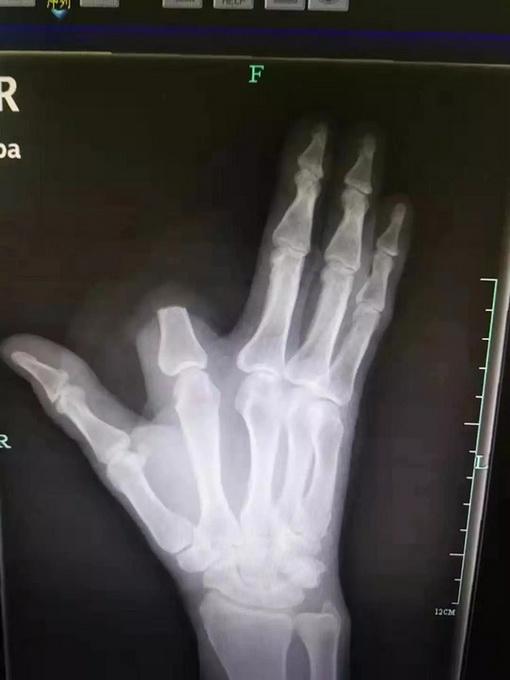

当李刚被送到医院时,医生们早已做好准备,他们迅速对李刚进行了紧急处理,首先对伤口进行了清洗和消毒,然后注射了抗蛇毒血清以中和毒液,经过一系列的抢救措施后,李刚的病情逐渐稳定下来,虽然他仍然需要留院观察一段时间以防止并发症的发生,但生命已经没有危险了。